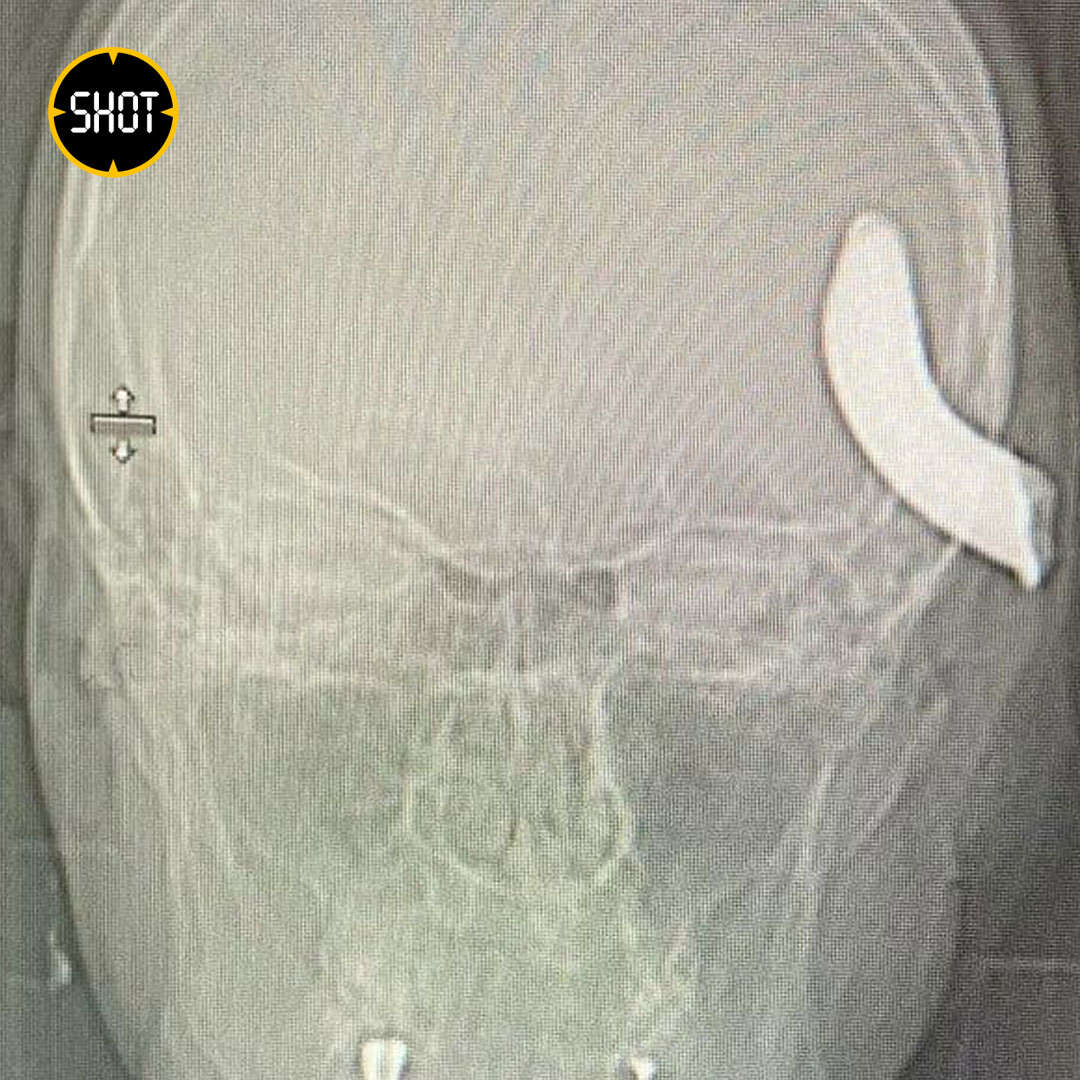

Как стало известно SHOT, 34-летний петербуржец Никита решил помочь другу в буксировке авто. Мужчины закрепили трос с помощью металлического крюка 6х4 см. Внезапно всё пошло не по плану: трос резко оторвался, а крюк с бешеной скоростью отлетел прямо в голову Никите и пробил череп.

Пострадавшего доставили в Елизаветинскую больницу. У мужчины началось нарушение речи и двигательных функций. Врачи сразу приступили к операции. Ему удалили часть костной ткани, провели трепанацию, и аккуратно достали крюк из черепа.